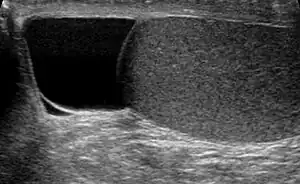

| Ultrasound of a testicle (grey) and a spermatocele (black). | |

The primary care physician may diagnose and manage benign causes of scrotal masses such as hydrocele, varicocele and spermatocele. However, if a "must not miss" diagnoses related to testicular masses such as testicular torsion, epididymitis, acute orchitis, strangulated hernia and testicular cancer is suspected, the family physician must refer to a urologist.[16] Finding a painless, cystic mass at the head of the epididymis that is clearly separate from the testicle can indicate a spermatocele. Shining a light through the mass through a process known as transillumination can also help differentiate between a fluid-filled cyst and a tumor, which would not allow as much light to pass.[17] If uncertainty exists, ultrasonography of the scrotum can confirm the presence of a spermatocele.[14] The location and history of any scrotal masses are crucial in determining whether or not the mass is benign or malignant.[18] Lab tests such as a complete blood count (CBC test) or urine test can also be conducted to check for any possible infection or signs of inflammation.[19]

Spermatoceles usually affect men who are middle-aged and can, although rarely, affect children during puberty.[23] The incidence rate is around 5-20% for children.[24] It is estimated that approximately 30 percent of men have been diagnosed with small spermatoceles while less have larger spermatoceles. The incidence of spermatoceles increases as men age.[25] Before puberty, children from the male sex may develop a similar benign mass called epididymis cyst. Although both epididymis cyst and spermatocele may be referred as the same, the epididymis cyst does not contain sperm and it can occur anywhere within the epididymis. It can be differentiated through an ultrasound imagining. Epididymis cysts larger than 10mm in diameter are recommended for surgery but if there is no problem then surgery is discouraged as it can affect fertility in the future.[11]